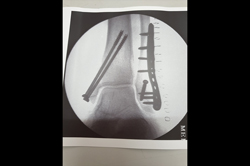

Ankle

Calcaneum